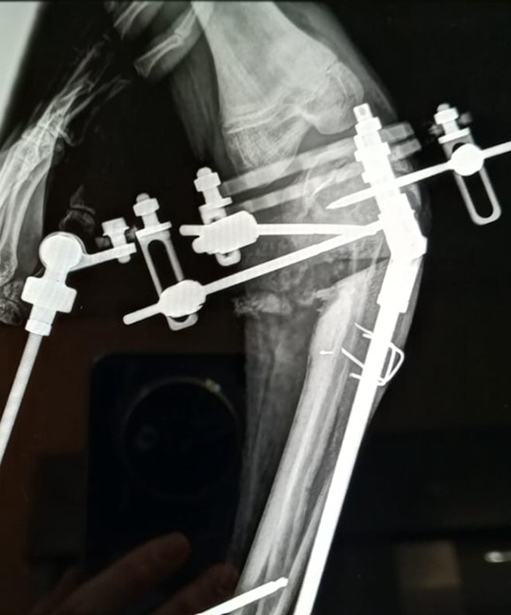

Figure 5. Post-operative AP radiograph after tibial osteotomy

Courtesy of Douglas W. Lundy, MD, MBA, FAAOS

Figure 6. AP radiograph demonstrating progressive correction of tibial deformity

Images Courtesy of Douglas W. Lundy, MD, MBA, FAAOS